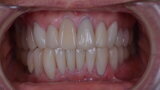

Figure 26 Closed mouth post op